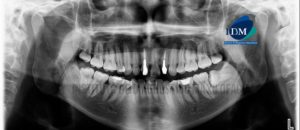

207 – Perforación en primera molar mandibular con conducto medio mesial y reabsorción radicular interna

Paciente masculino de 23 años de edad, es referido al Instituto de Diagnóstico Maxilofacial (IDM) para evaluación tomográfica de la pieza 3.6. En la radiografía